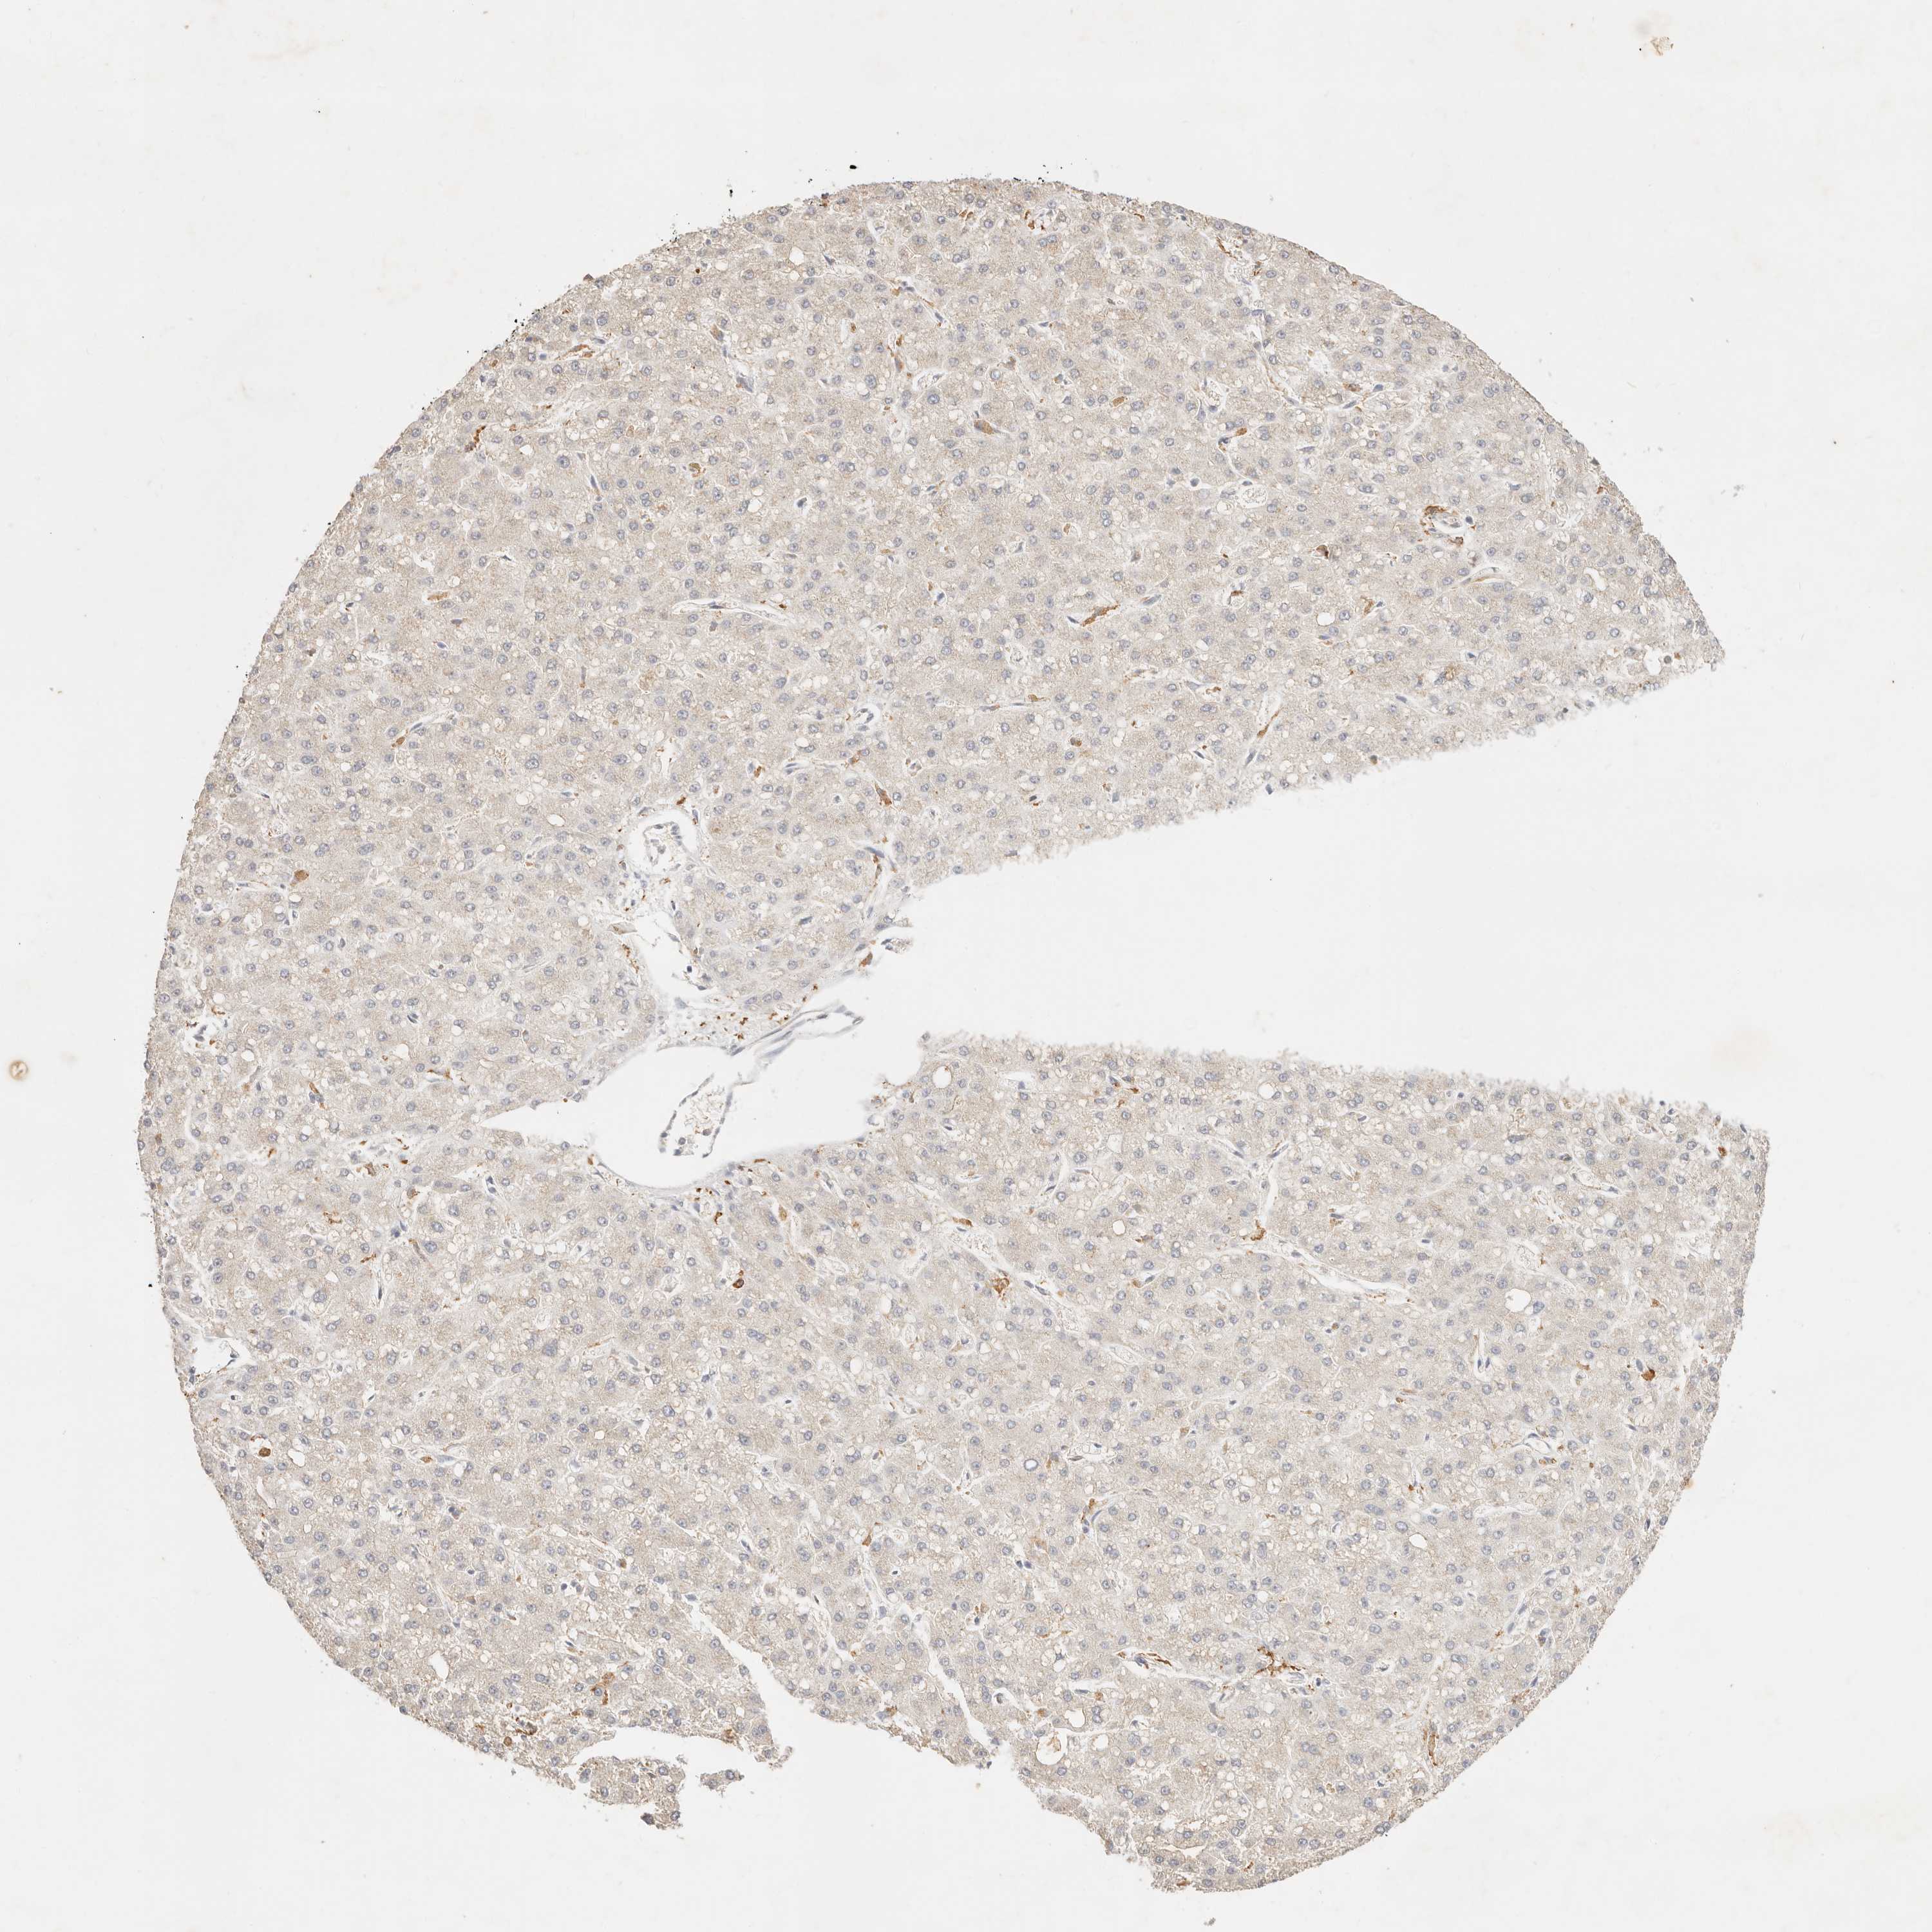

LIVER CANCER - Protein expressioni

A mouse-over function shows sample information and annotation data. Click on an image to view it in a full screen mode. Samples can be filtered based on level of antibody staining by selecting one or several of the following categories: high, medium, low and not detected. The assay and annotation is described here.

Antibody stainingi

Antibody staining in the annotated cell types in the current human tissue is reported as not detected, low, medium, or high, based on conventional immunohistochemistry profiling in selected tissues. This score is based on the combination of the staining intensity and fraction of stained cells.

Each image is clickable and will lead to virtual microscopy that enables deeper exploration of all samples and also displays staining intensity scores, fraction scores and subcellular localization as well as patient and tissue information for each sample.

Antibody HPA028587

Staining

High

Medium

Low

Not detected

Intensity

Strong

Moderate

Weak

Negative

Quantity

>75%

75%-25%

<25%

None

Location

Nuclear

Cytoplasmic/membranous

Cytoplasmic/membranous,nuclear

Cholangiocarcinoma

Carcinoma, Hepatocellular, NOS